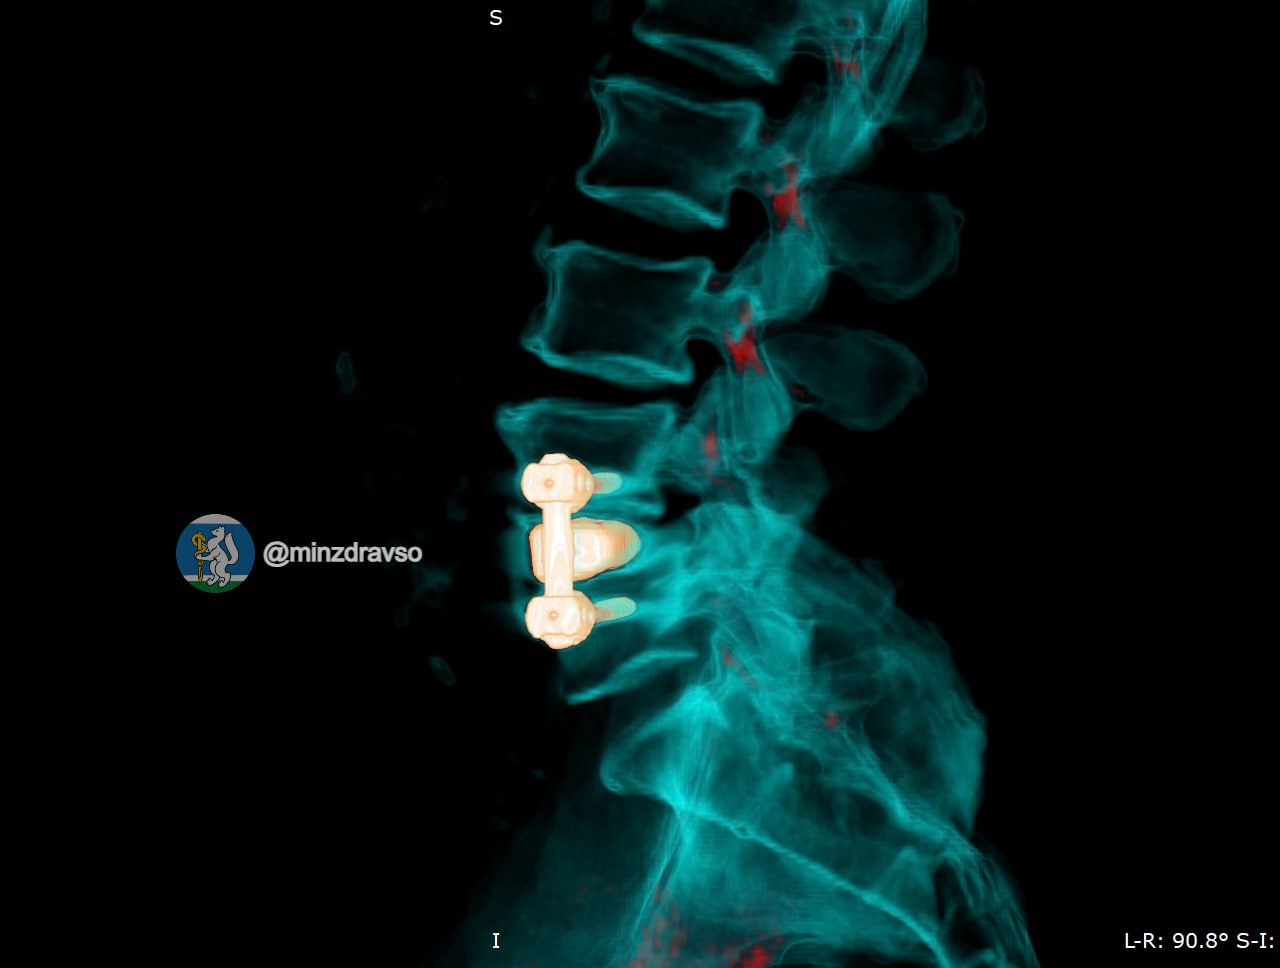

«В таких случаях недостаточно просто убрать инфекцию. Необходимо восстановить стабильность позвоночника, чтобы человек мог жить активно. Мы применили комбинированную реконструкцию с использованием современных технологий», — пояснил оперирующий нейрохирург госпиталя Иван Доценко.

Пациенту установили титановый 3D-имплант, изготовленный по индивидуальным параметрам. Фиксацию выполнили российскими спонгиозными винтами. Уже в первые сутки после операции болевой синдром полностью купировался, пациент самостоятельно встал и начал ходить.